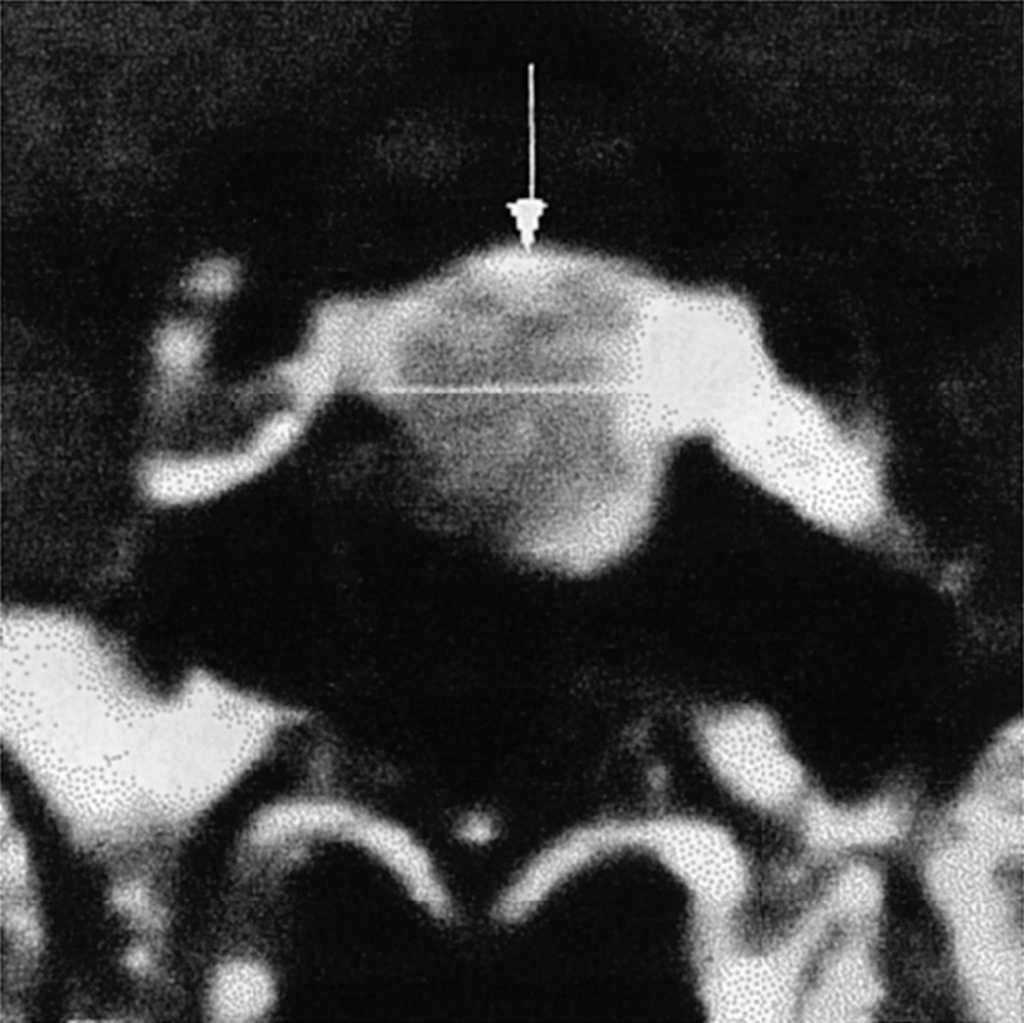

El estudio de imagen muestra un macroadenoma hipofisario con extensión supraselar mínima (fig. 1) y la campimetría es normal.

Figura 1. El estudio de imagen con resonancia magnética nuclear muestra en la sección coronal un macroadenoma hipofisario con expansión supraselar mínima.